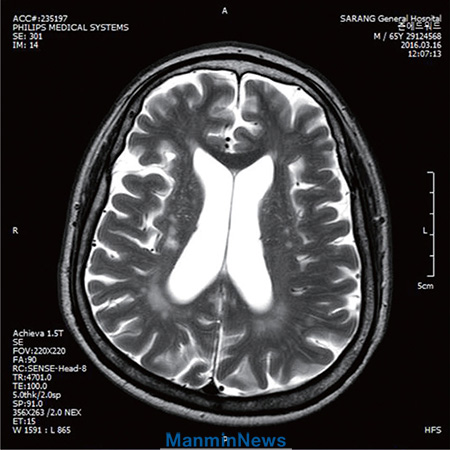

核磁共振成像(MRI)结果:除了老化现象不见脑梗塞症状。

2015年1月左右,因运动时疼痛反复,就到医院做了检查。经核磁共振成像(MRI)诊断,结果在腰椎部位发现炎症,椎骨和腰肌出现异常。

接受祷告前:两侧腰肌内形成直径六至七厘米的脓肿。

接受祷告后:两侧腰肌内直径六至七厘米的脓肿消失。